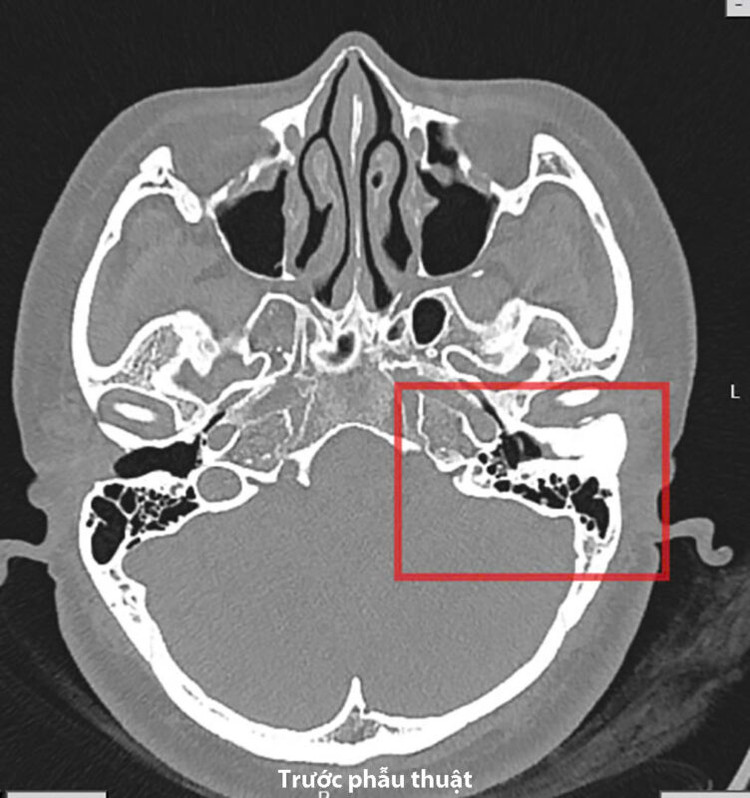

![]() |

| Hình ảnh khối đậm độ như xương làm chít hẹp gần như toàn bộ ống tai trái của bệnh nhân. Ảnh BVCC |